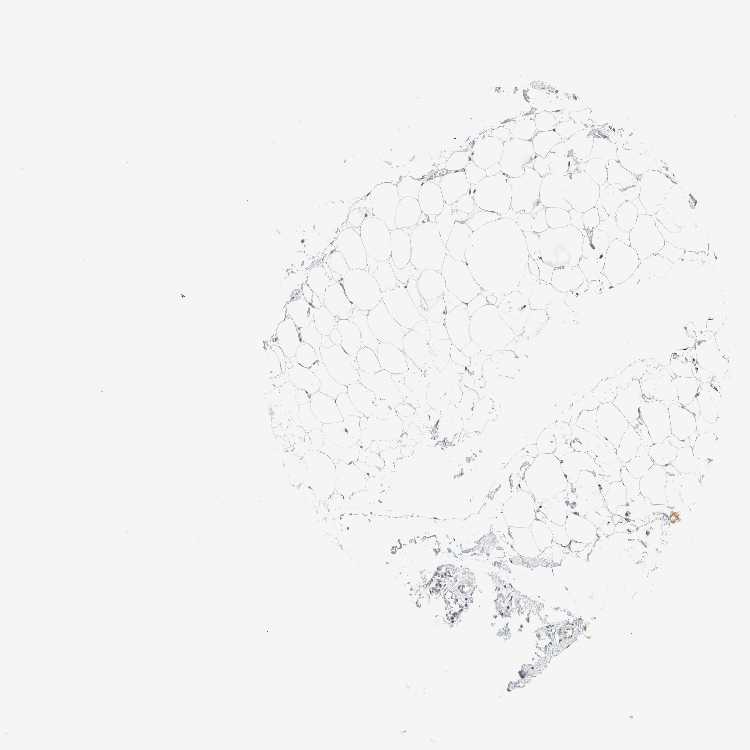

SOFT TISSUE 1 - Antibody stainingi

Antibody staining in the annotated cell types in the current human tissue is reported as not detected, low, medium, or high, based on conventional immunohistochemistry profiling in selected tissues. This score is based on the combination of the staining intensity and fraction of stained cells.

Each image is clickable and will lead to virtual microscopy that enables deeper exploration of all samples and also displays staining intensity scores, fraction scores and subcellular localization as well as patient and tissue information for each sample.

Antibody HPA023865

Chondrocytes High

Fibroblasts Low

Peripheral nerve High